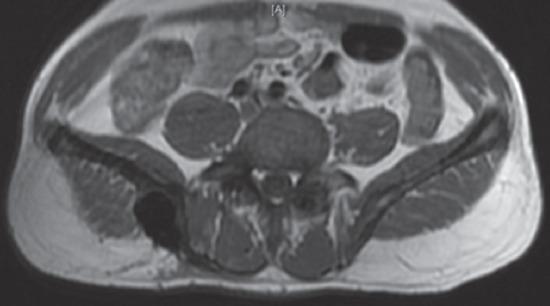

一名 40 岁男性因背痛就诊,经评估诊断为多骨型 PDB。他接受了静脉注射双膦酸盐、钙剂和维生素 D 补充剂治疗。在无症状的 3 年后,他出现了累及髂骨和骶骨的臀肌肿块,活检确诊为 GCT。尝试了系列血管栓塞术,但肿块仍进展,因此进行了手术,切除并刮除病变。2 年后他出现局部复发,伴有大量软组织成分。开始使用地诺单抗(一种 RANKL 抑制剂),目的是降低病变分期。患者在 6 次给药后显示出良好反应,软组织肿块缩小,随后接受了部分 T-1 型内部半骨盆切除术和骶骨刮除术。目前,患者在 15 个月的随访中无症状。